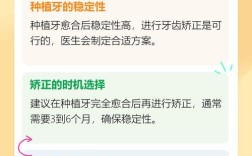

- 牙槽骨少可以种牙,但通常需要额外的骨增量手术。

- 现代技术(GBR、上颌窦提升、骨劈开、自体骨移植等)能有效解决骨量不足的问题。

- 骨增量手术会增加治疗周期(通常需要3-9个月甚至更长)和费用。